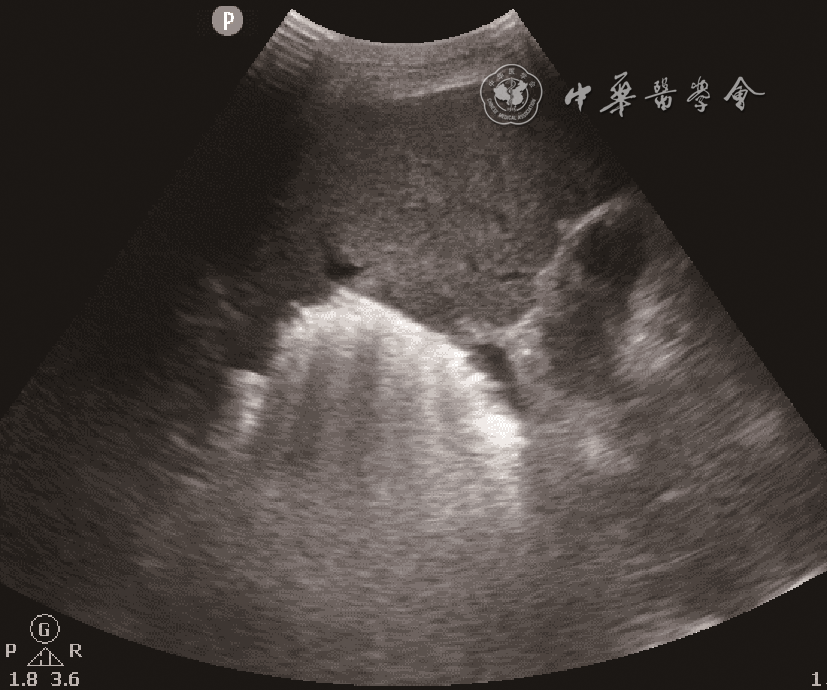

入急诊科时患者血压为60/29 mmHg(1 mmHg=0.133 kPa),心率为143次/min,末梢氧饱和度低,气管插管呼吸机辅助通气。11月26日急诊床旁超声检查提示:肝内多发高回声包块并肝静脉内气体样强回声漂动入下腔静脉、右心,肺动脉内可见大量气体样强回声,考虑产气型肝脓肿破裂(图12动态图1)。急诊平扫CT检查提示:肝多发类圆形混杂气体密度灶,肝内外胆管扩张、积气(图3)。当日血培养检出高黏性肺炎克雷伯菌(Klebsiella pneumoniae,KP),菌拉丝阳性,毒理强。血常规检查结果如下:快速C反应蛋白:243.18 mg/L(正常值范围≤10.00 mg/L);白细胞:15.93×109/L[正常值范围(3.50~9.50)×109/L];中性粒细胞百分比:93.5%(正常值范围40.0%~75.0%);血糖:38.7 mmol/L(参考值3.9~6.1 mmol/L);谷草转氨酶:247 U/L(参考值15~40 U/L);碱性磷酸酶:369 U/L(参考值45~125 U/L);谷氨酰基转移酶:349 U/L(参考值10~60 U/L);血肌酐:195 μmol/L(参考值59~104 μmol/L);尿酸:772 μmol/L(参考值208~428 μmol/L);尿常规:葡萄糖(++++)(正常值:阴性);血白介素6:2887.00 pg/ml(正常值范围0.00~7.00 pg/ml)。

图2 超声声像图示右心房内大量“气体样”强回声

临床对于脓肿自发破裂的诊断相对困难。脓肿破裂情况下患者病情往往危重,不适宜行CT检查,床旁超声检查则成为首选。产气型肝脓肿的超声表现以脓腔内片状强回声或肝内胆管系统积气多见9。Pham等10报道1例肝脓肿破裂引起气腹及腹膜炎的病例,术前超声、CT检查均未确诊,后通过剖腹探查确诊。既往报道了1例肝脓肿破裂引起肝静脉积气的患者,超声能实时、快速地观察肝静脉内气体动态变化,这为肝脓肿破裂的诊断提供了有力证据,从而为临床治疗提供更好的指导11。超声可以观察到肝静脉内气泡的有节律的与心率相关的运动,可用于区分气泡是位于门静脉系统、肝内胆管还是位于肝静脉系统12。本病例中CT检查同样发现肝内积气,但将肝静脉内积气误认为了肝内胆管积气。本病例超声显示肝静脉内大量气泡有节律地向下腔静脉内漂动,气泡再通过下腔静脉漂动至右心、肺动脉。这种表现提示血行播散,或可为KP肝脓肿的肝外血行播散,如眼内炎、中枢神经系统感染、坏死性筋膜炎等的诊断提供线索。